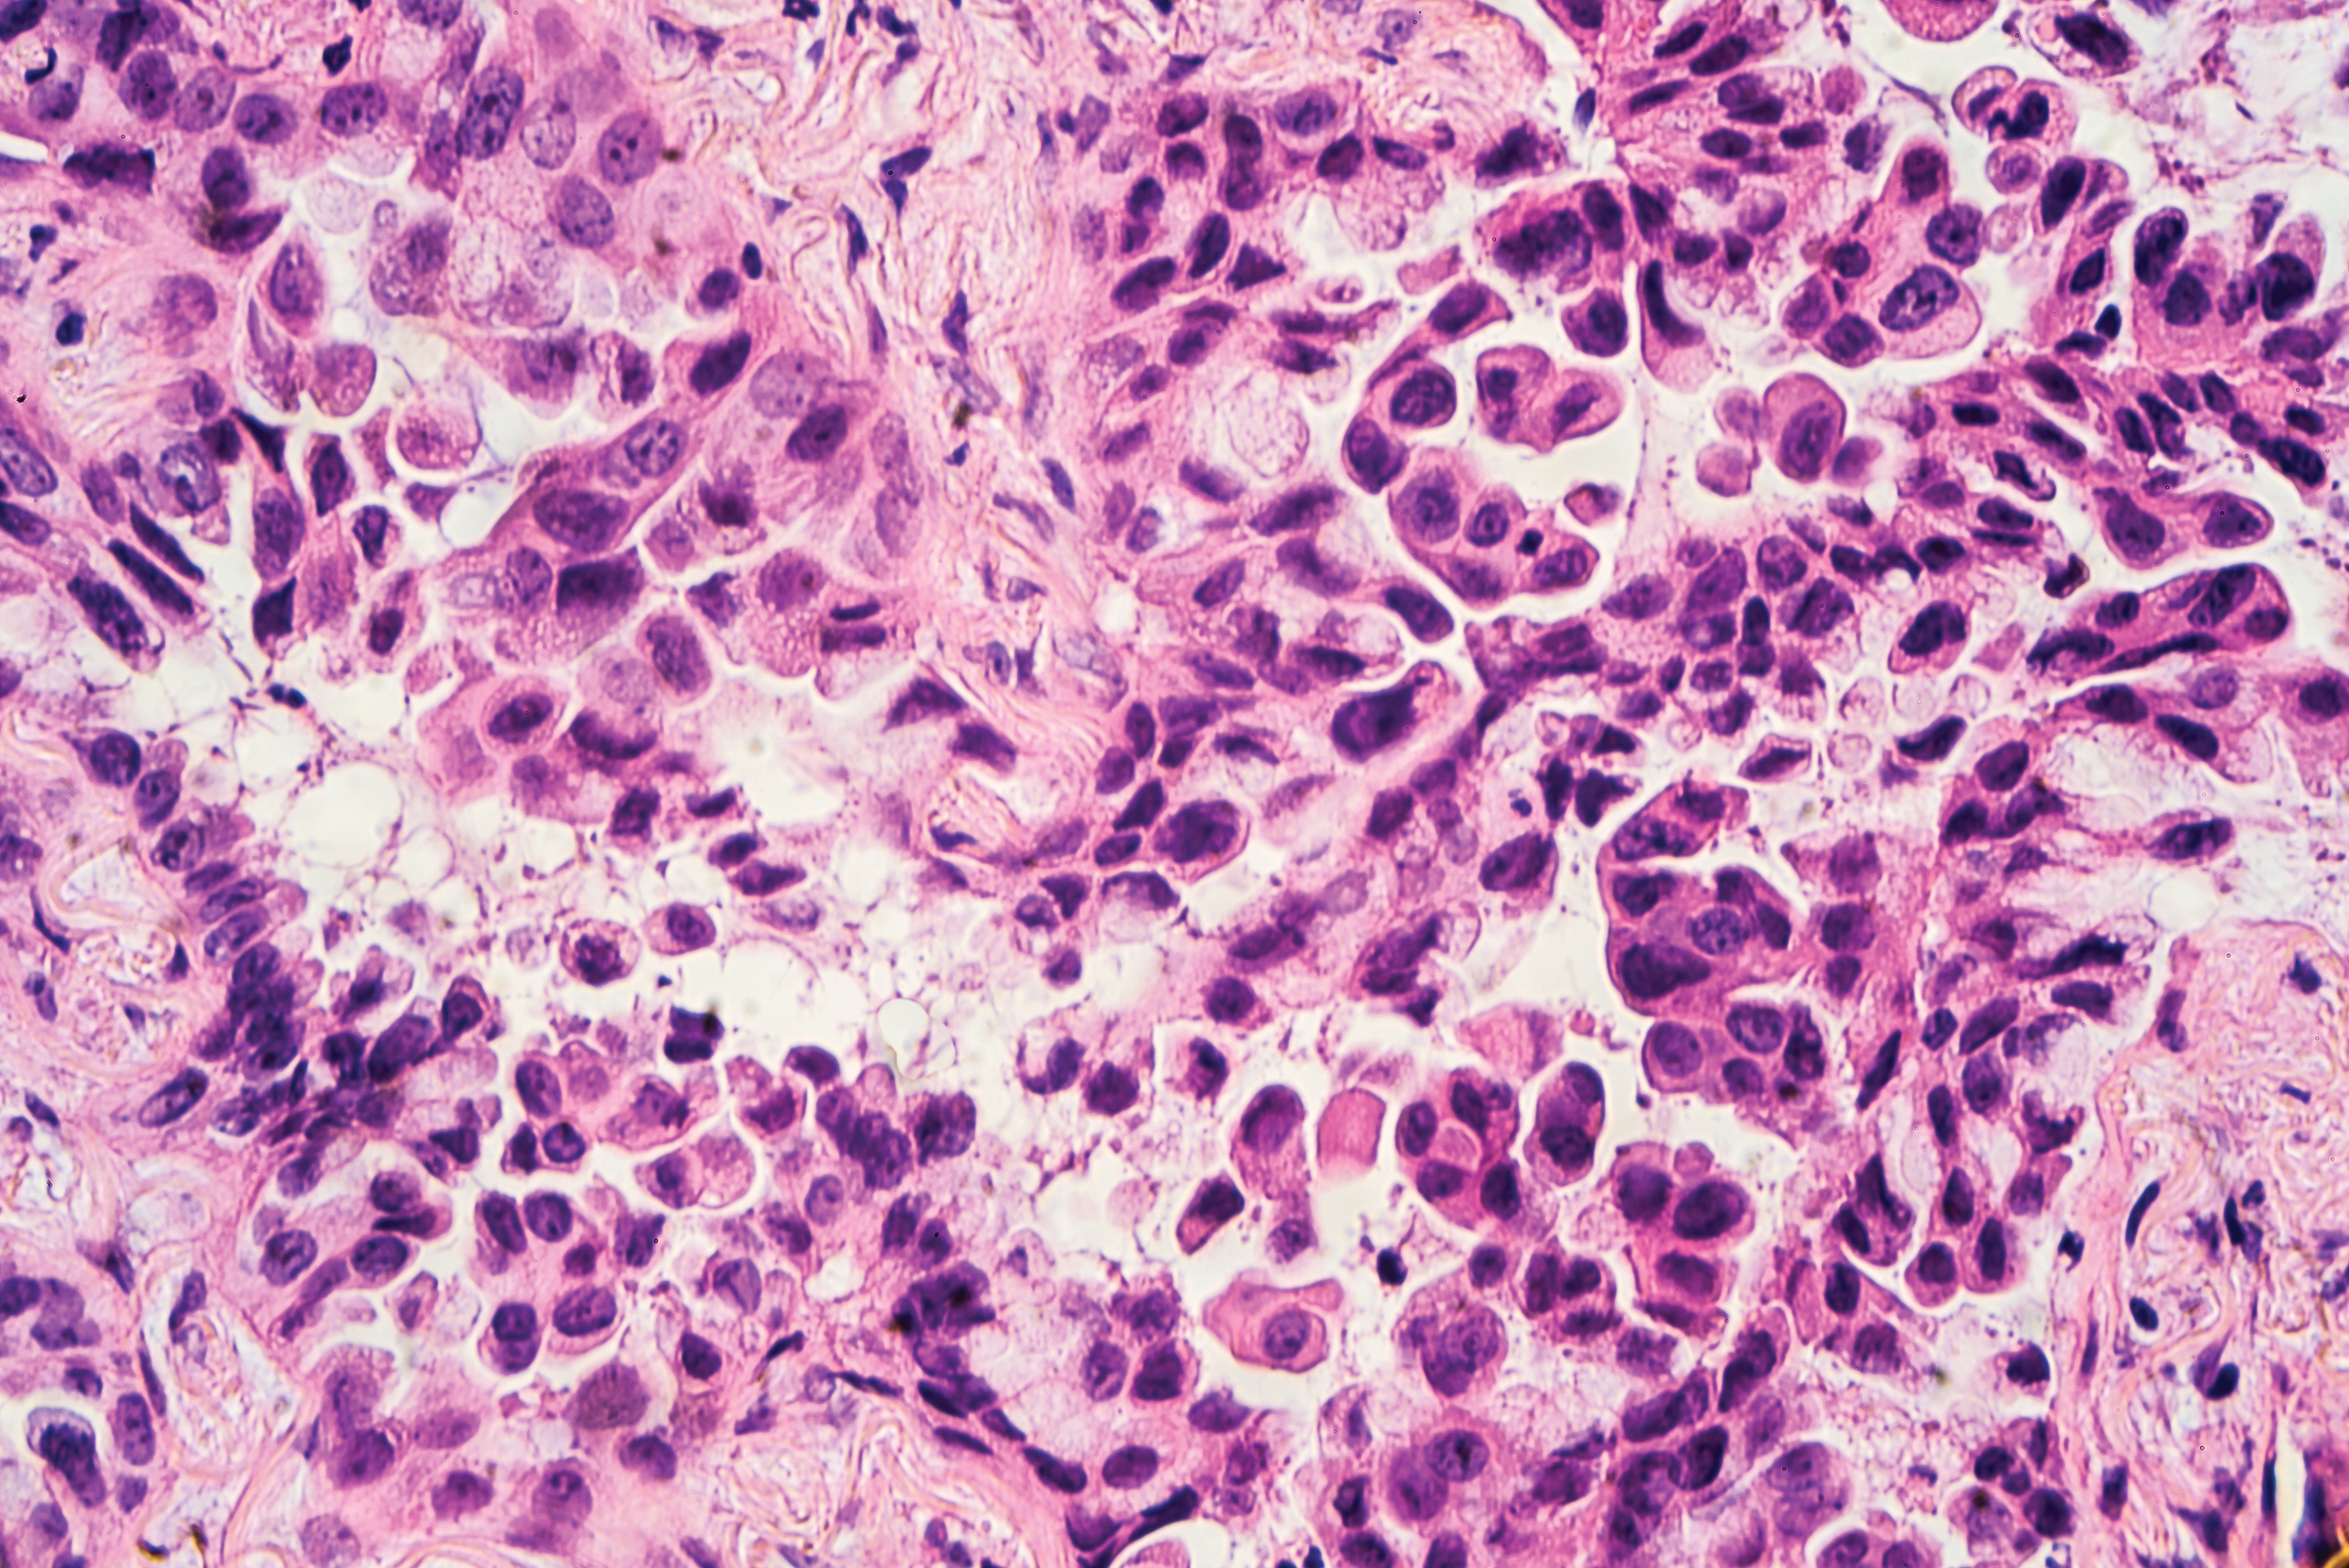

L’histologie est l’étude des tissus. Le tissu tumoral sera alors examiné plus en détail. Le prélèvement de tissu peut être réalisé soit par bronchoscopie soit par ponction transthoracique (à travers la cage thoracique). Des échantillons de tissu seront prélevés dans les poumons et la tumeur, puis examinés au microscope.

Grâce aux propriétés histologiques, le CPNPC peut être divisé en quatre sous-groupes :

• Adénocarcinome (se développe à partir des cellules du tissu glandulaire du poumon)

• Carcinome épidermoïde (se développe à partir des cellules de la muqueuse dans la région des bronches)

• Carcinome à grandes cellules (lorsqu’il n’y a ni adénocarcinome ni carcinome épidermoïde)

• Autres carcinomes pulmonaires non à petites cellules